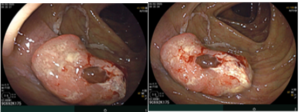

Ca lâm sàng: Chẩn đoán, tư vấn di truyền và điều trị bệnh nhân mắc ung thư đại tràng có tính chất gia đình tại Trung tâm Y học hạt nhân và Ung bướu – Bệnh viện Bạch Mai

Ca lâm sàng: Chẩn đoán, tư vấn di truyền và điều trị bệnh nhân mắc ung thư đại tràng có tính chất gia đình tại Trung tâm Y học hạt nhân và Ung bướu – Bệnh viện Bạch Mai GS.TS.Mai Trọng Khoa1,2, PGS.TS.Phạm Cẩm Phương1,2,ThS.BS.Phạm Minh Lanh1,2, SV.Nguyễn Thị Hồng...